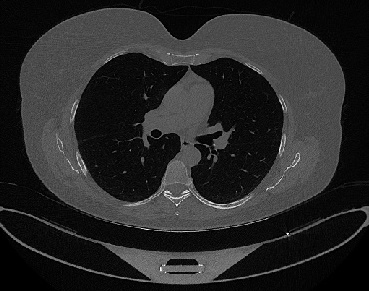

Figure 1 shows four CT scan slices, two from a non-COVID-19 CT scan, on the left and two from a COVID-19 scan, on the right. Bilateral ground glass regions are seen especially in lower lung lobes in the COVID-19 slices.